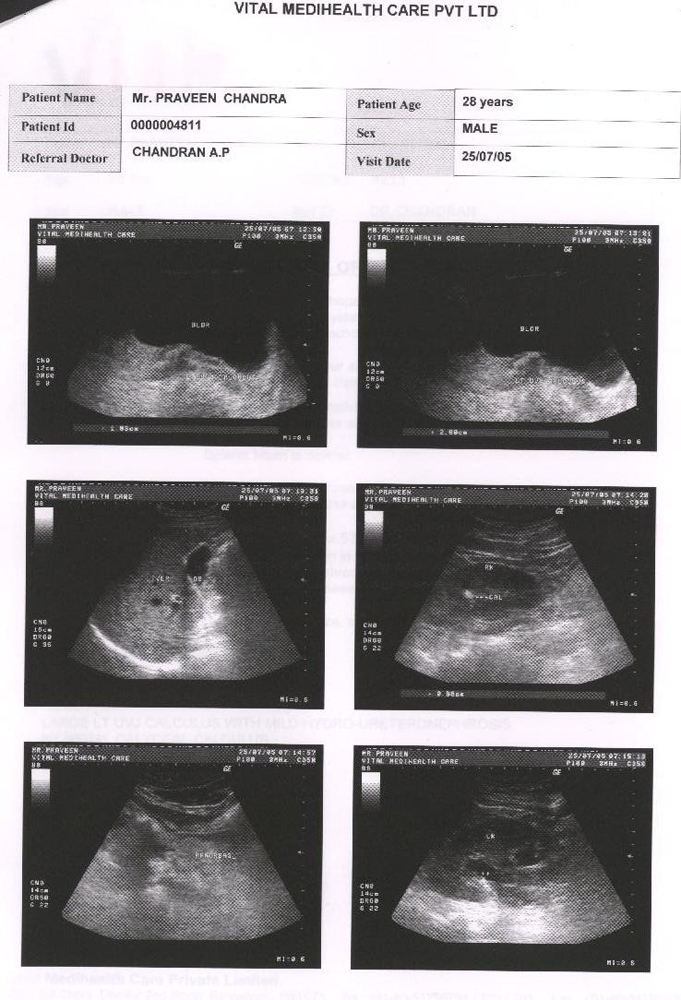

Condition of patient in beginning of Homoeopathic treatment for Kidney Calculus